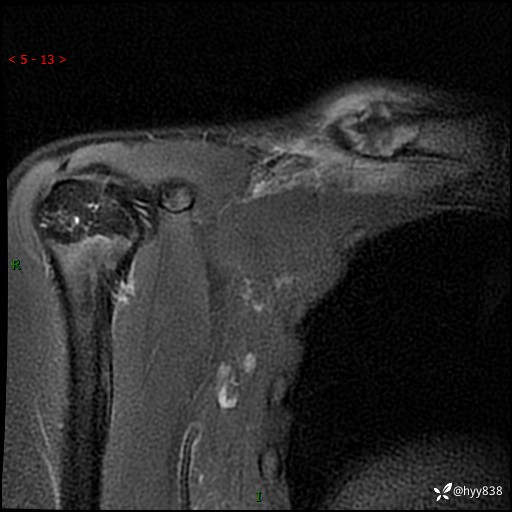

MRI(cor T1WI+T2WIfs+axi T2WIfs)